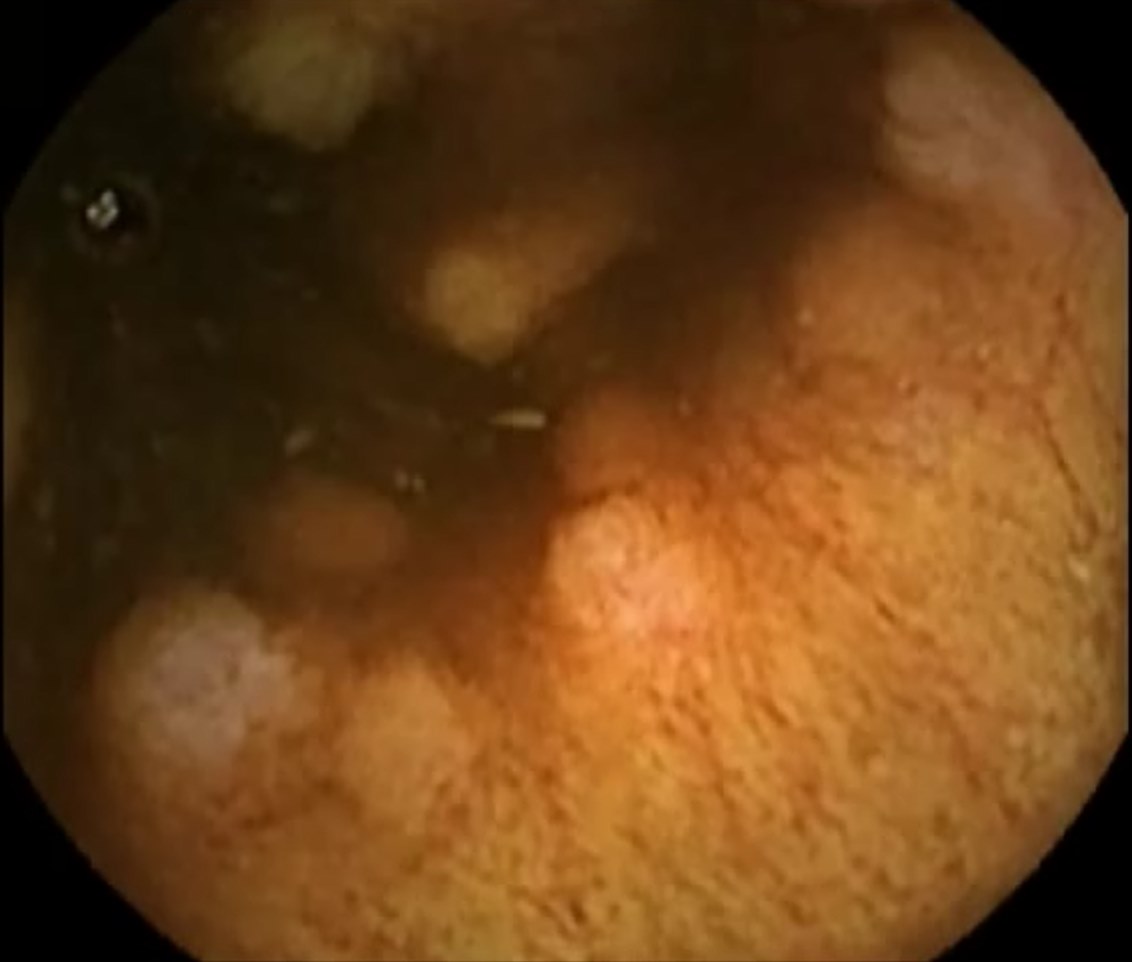

Capsule Endoscopy: Ileum Terminale, Lymphoid Hyperplasia

Capsule Endoscopy: Ileum Terminale, Lymphoid Hyperplasia. Just click on a picture!